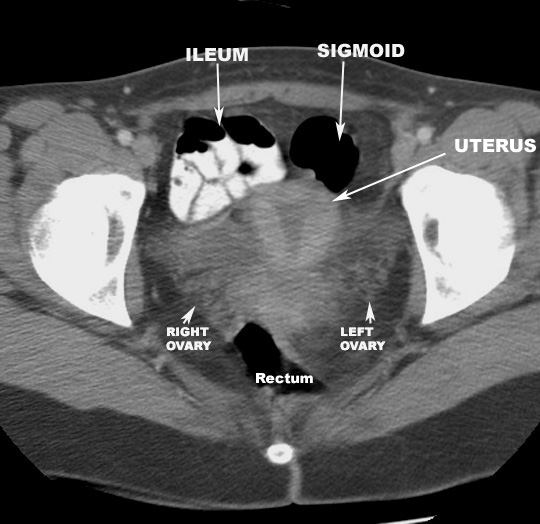

CT Pelvis |